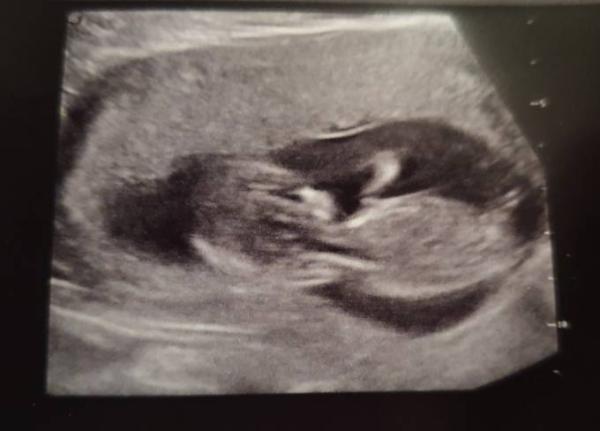

Komme gerade vom Arzt zurück. Alles wunderbar. Der Bauchzwerg hat richtig wild gezappelt und sogar gewunken. Bin jetzt in Woche 13/4. ET stimmt wahrscheinlich nicht, aber er wollte es heute nicht ändern. Erst in ca. 7 Wochen beim nächsten US. Outing gab es nicht, aber ist nicht schlimm. Hab was für die Schilddrüse bekommen, ist aber alles im grünen Bereich. Jetzt heißt es wieder 4 Wochen warten.

Bild zu Zurück vom FA - Forum für Juli - Mamis

Süßes Bild! Du bist 3 Tage vor mir, da hat man eine Ahnung, wie der eigene Zwerg aussieht. Ich nehm auch Schilddrüsen Medis, wie kam dein Arzt drauf? Übers Blutbild? Soll der ET vorgezogen werden?